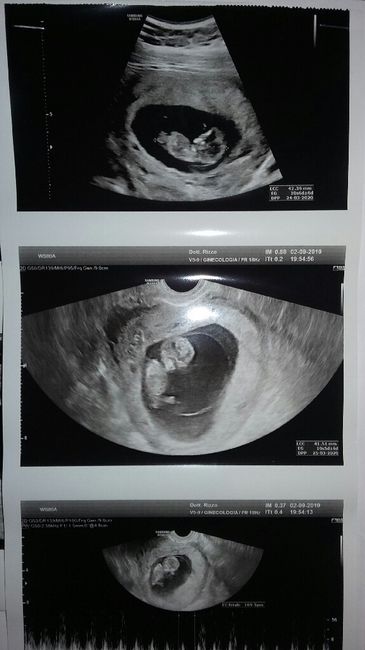

Screening fatto venerdì tutto ok, esito con bi test ritirato ieri rischio intermedio per la sindrome di down......mi consigliano di fare l'esame del DNA fetale che farò lunedì prossimo, però l'ansia mi sta assalendo.....C'è qualcuna che ha avuto la...